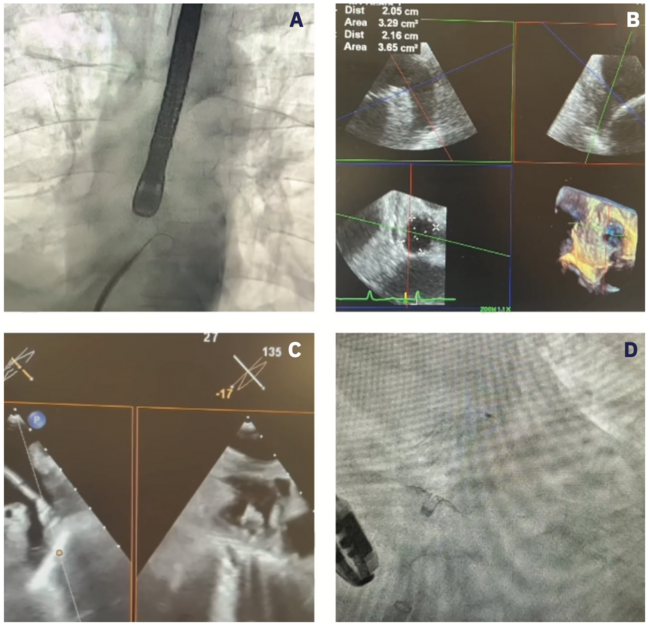

If sizing is acceptable and thrombus is ruled out, ultrasound-guided micropuncture access is achieved and the Watchman 12 French (F) TruSeal Access System (Boston Scientific) with the VersaCross Connect Transseptal Dilator (Baylis Medical) is placed into the superior vena cava. Systemic heparin is administered and therapeutic activating clotting time is achieved. The sheath is pulled down to the fossa ovalis, and a mid and posterior crossing position is confirmed with TEE. Using the VersaCross Transseptal Platform, radiofrequency is used to cross the septum and the sheath is advanced into the LA (Figure 2A/Video 1). LA pressure is obtained. Next, a pigtail catheter is placed into the LAA. CT angiography of the LAA is performed in a right anterior oblique 30º caudal position. Sizing of the device is determined by LAA assessment on TEE (Figure 2B/Video 1). Then, the pigtail catheter is removed, and the Watchman system is prepared and delivered to the LAA. The device is passively exposed to form a “FLX-Ball,” which is advanced and deployed under TEE guidance (Figure 2C/Video 1). The system is held in place and the device is fully deployed. Using TEE, device assessment is performed to evaluate for PASS criteria (positioning, anchoring, size and seal), which must be met before the device is released. If PASS criteria is not met, the device can be recaptured (as many times as needed) and repositioned or exchanged for an alternatively sized device.

Video 1. Watchman FLX deployment using multimodality imaging. (A) Fluoroscopy demonstrating a mid and posterior transseptal puncture with the VersaCross Connect System (Baylis Medical) (video). (B) Two-dimensional and 3-dimensional TEE imaging demonstrating measurements of the LAA. (C) Watchman “FLX-Ball” being advanced and positioned for deployment under TEE guidance (video). (D) Watchman FLX #24 device deployed on fluoroscopy.